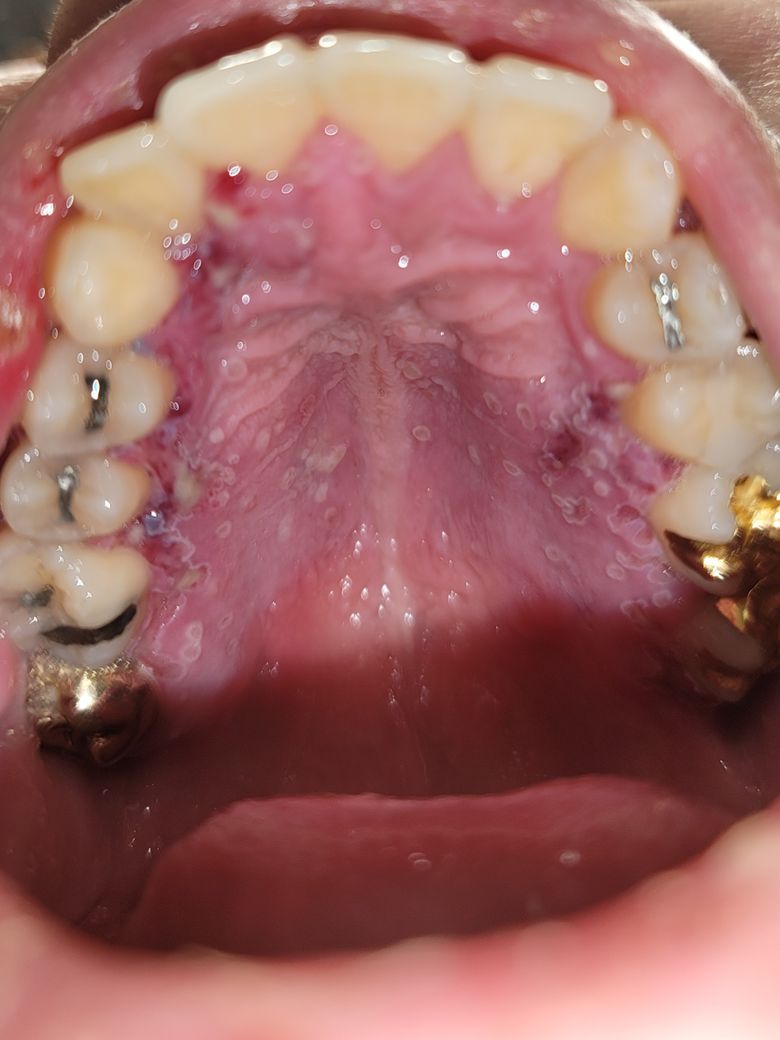

사진(혐 주의)과 같이 입 안 전체적으로 구내염이 심하게 났어요.

음식을 도저히 못씹을 정도라 흰 쌀죽을 믹서기에 갈아서 먹고 있어요.